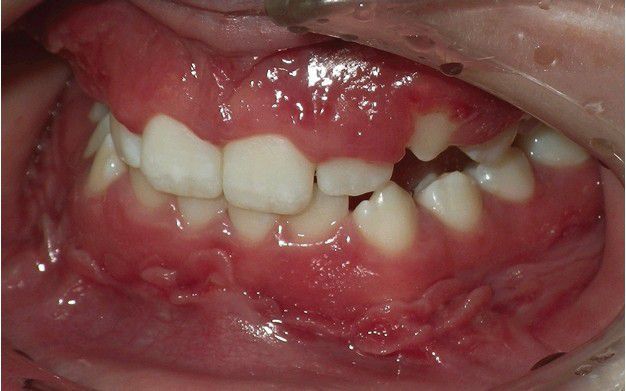

Orofacial Granulomatosis

. Hyperplastic mucosa noted bilaterally in the mandibular mucobuccal fold.